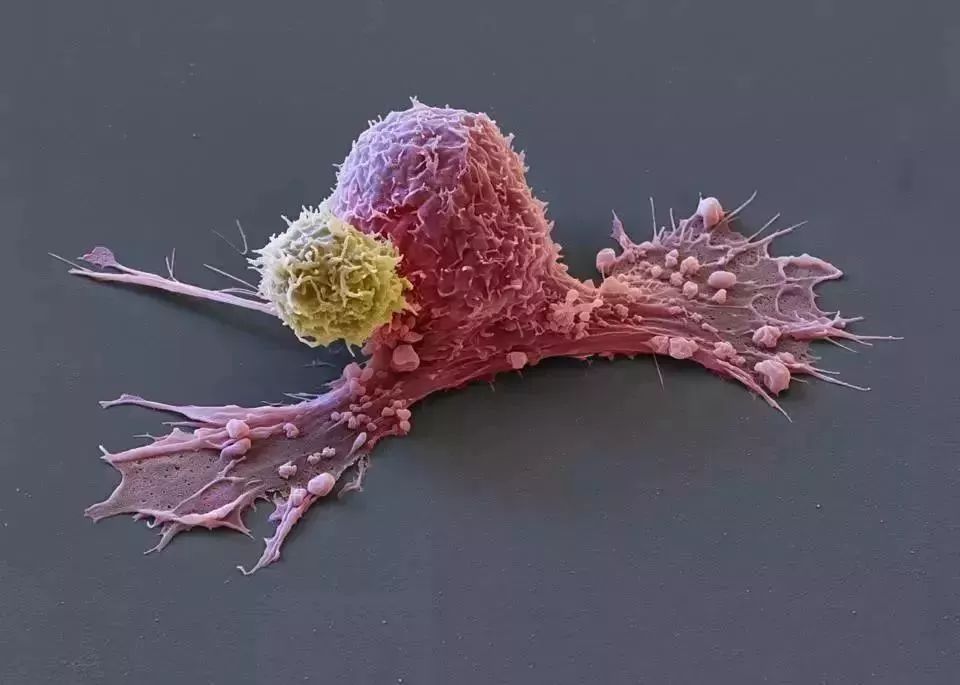

癌细胞一旦在体内找到了合适的落点

“定居”下来,灾难就降临了。它凭借顽强

的生存能力和无限繁殖的特点在身体

各个部位扩散蔓延和制造伤害

虽然在生物体内威风凛凛,几乎无懈可击

但如果把它取出体外培养基中培养

它又变成孱弱的“懦夫”,通常不出两天就死亡

免疫细胞大战癌细胞

和其它癌细胞一样,海拉细胞也是由正常

细胞癌变得来,具有错误填充的基因组

正常人体细胞中含有 46 条染色体

而经过突变的癌细胞染色体数目多达

76~80 条。这是因为基因组中出现未检测

到的细胞分裂时发生错误累积。它们异于

常态细胞地表现为增殖速度激增

同时在人体内逃避了细胞凋亡

但海拉细胞的增殖速度比普通的癌细胞更快